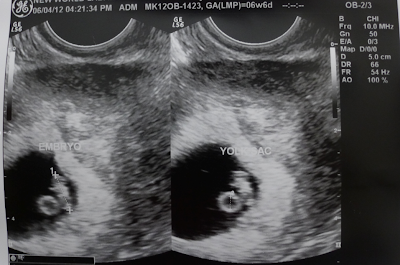

She has developed a small bump on her belly that is now starting to get bigger... And as you all know, that's me growing inside her tummy.

I am now nearly 10 weeks and I am now as big as the size of a grape.